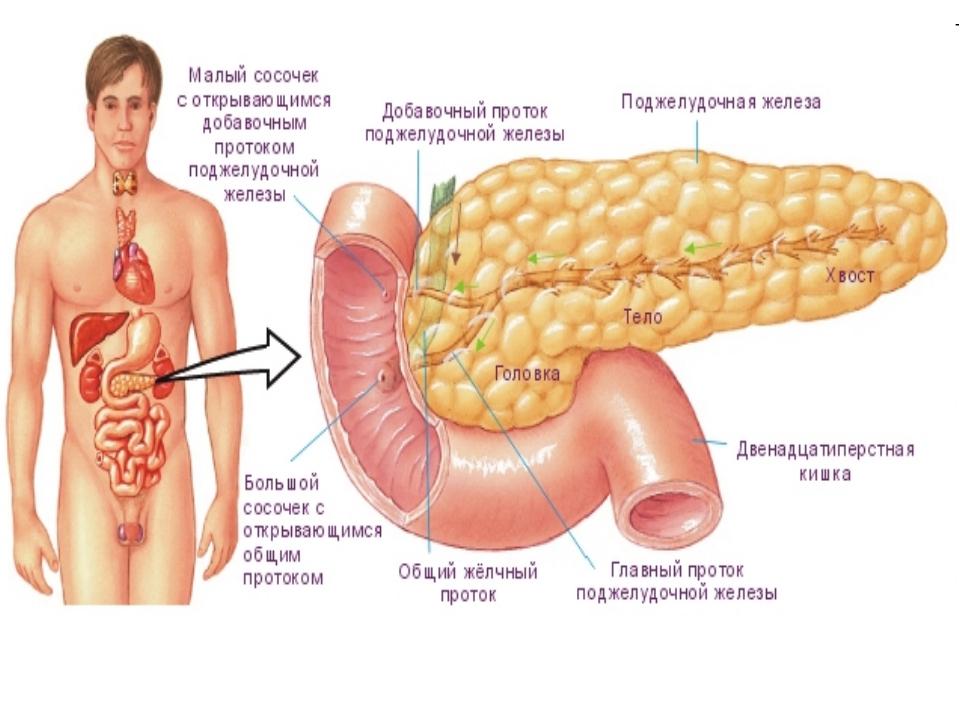

Анатомическое расположение поджелудочной железы

ПЖ располагается в брюшной полости, ближе к I–II позвонкам поясничного отдела позвоночника. Орган плотно крепится на задней стенке желудка, а 12-перстная кишка окружает ее, поддерживая в необходимом положении.

По анатомическому строению орган делится на 3 составных части: это головка, тело и хвост. Головкой ПЖ обращена к желчному протоку, тело находится за желудком, ближе к его нижней части. Рядом с телом в норме располагается поперечно-ободочная кишка. Хвостом ПЖ обращена к селезенке, и уходит к левому подреберью. По отношению к пупку, со стороны брюшной стенки, ПЖ расположена над ним, на 5-10 см выше.